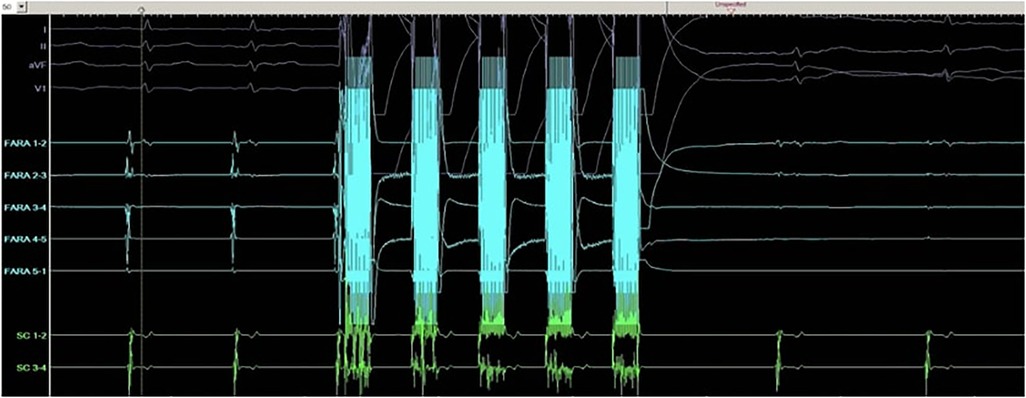

PFA is a nonthermal technique to ablate cells. In PFA, high electric field gradients are applied to cardiomyocytes using D.C. energy, which is rapidly pulsed. This process creates small pores in the cell membrane, known as electroporation, which makes the membrane more permeable. The strength of the electric field applied determines whether the effect is reversible or irreversible, with reversible electroporation repairing cell membranes and greater electric field application causing irreversible cell death through apoptosis or necrosis (Figure 1) (6).

Figure 1